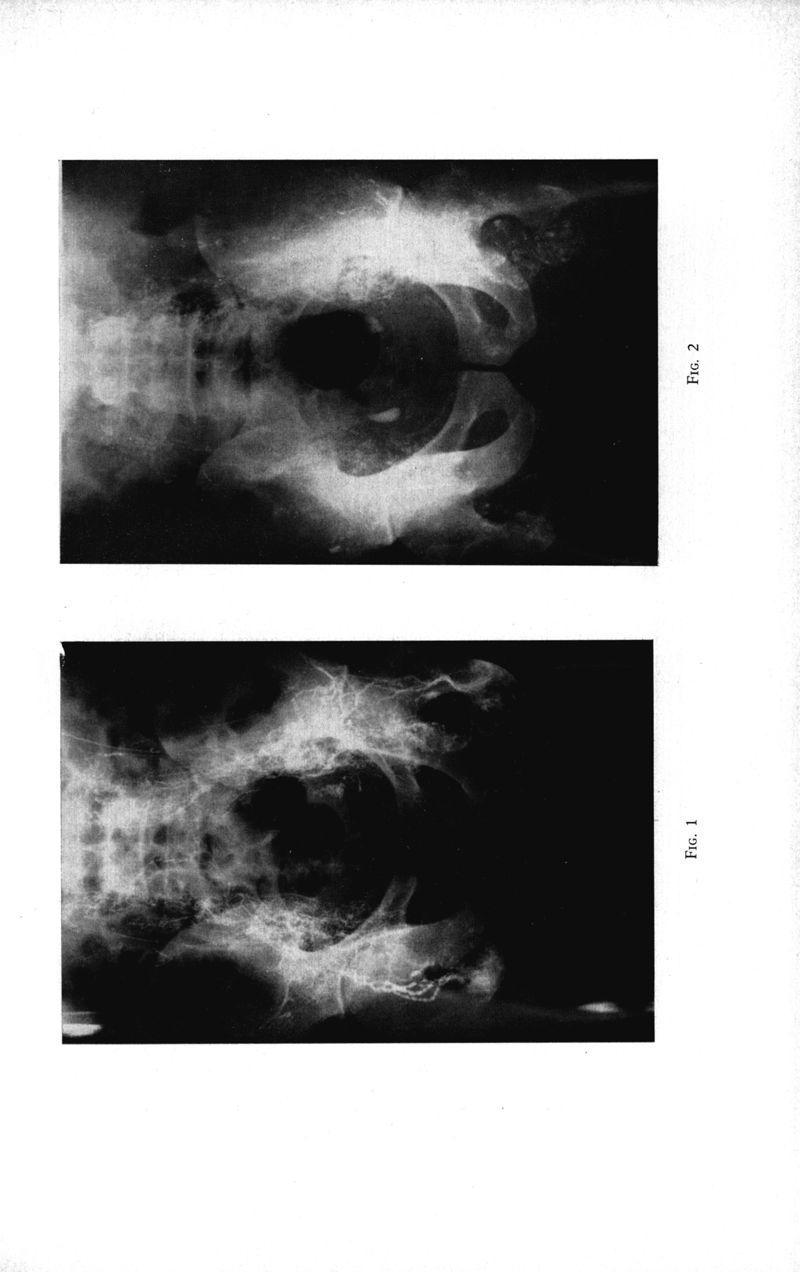

Marseille : Ecole d'application et centre d'instruction et de recherche. Service de santé des troupes de marine,

1969.